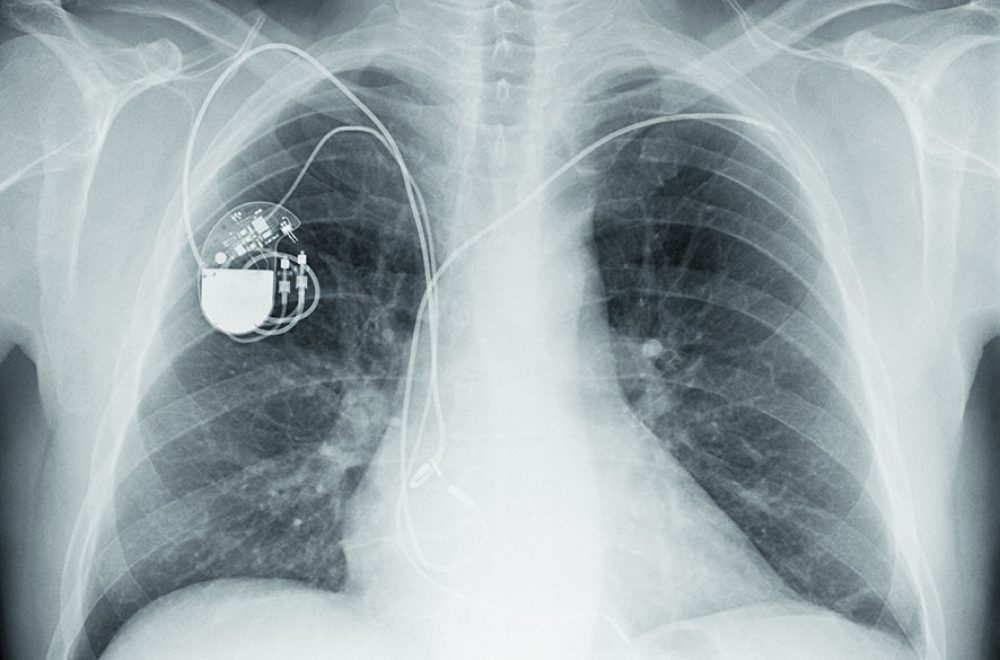

De pacemaker, de ‘hartprikkelaar’, is één van de hulpmiddelen die ervoor zorgt dat veel mensen nu in leven blijven, terwijl zij twintig of dertig jaar geleden onherroepelijk zouden zijn gestorven aan een plotselinge hartstilstand of een ernstige ontregeling van het hartritme.

Maar toch, voortbordurend op de ervaringen uit dit bijzondere verhaal, leidden experimenten met stroomtoediening pas in 1930 tot de komst van de allereerste externe pacemaker. Is de pacemaker van nu nauwelijks groter dan een plat lucifersdoosje, toen was sprake van een enorm apparaat waarmee via naalden tot op het hart stroomstootjes konden worden toegediend.

De pacemaker van nu is nauwelijks groter dan een plat lucifersdoosje, toen was er sprake van een enorm apparaat